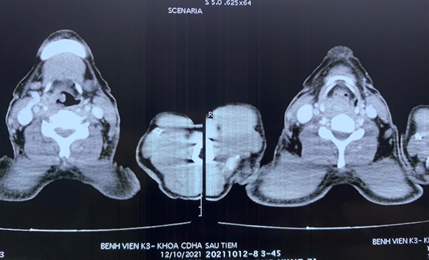

Hình ảnh được chụp sau khi tái tạo đường ăn cho bệnh nhân ung thư hạ họng